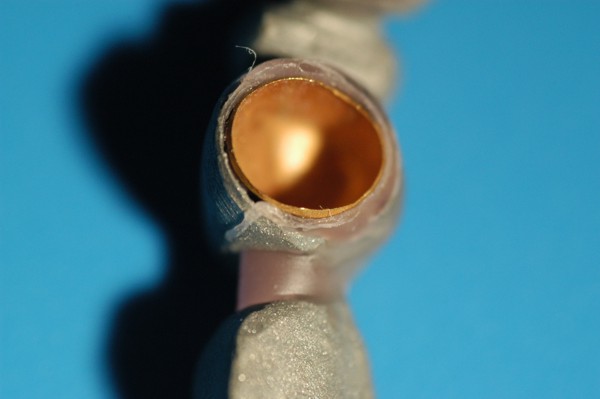

ABSTRACT La literatura oclusal se ha encargado de describir distintas funciones de la misma a través de los tiempos. El presente caso se realiza en forma de sobredentadura (over denture) debido a que la carencia de reborde óseo en el sector anterior verificado tanto clínicamente como mediante telerradiografía , impedía llevar a cabo una prótesis fija , por lo que se optó por un sistema de pilares ceramizados y paralelizados mediante el sistema SIRIUS, sobre seis implantes, y la conexión a una estructura de metal cerámica FIJA AMOVIBLE, mediante coronas telescópicas galvanizadas, otorgando al sistema la rehabilitación mediante una PIA(Prótesis Implanto Asistida con reposición ósea y gingival mediante porcelana rosa.) MATERIAL Y MÉTODOS: IMPLANTES:KLOCKNER SK-T.T.S. MONTAJE Y REGISTROS: ARCO FACIAL ESTÁTICO Y ARTICULADOR PRIMARIA: Abuttmets Ceramizados (I.P.S. D.SIGN IVOCLAR) SECUNDARIA: Cofias Galvanoformadas (AURO GALVAN CROWN WIELAND) TERCIARIA: Férula de Porcelana sobre Metal (I.P.S. D. SIGN IVOCLAR) CEMENTADO INTERFASE: NIMETIC CEM-ESPE DESARROLLO Se presenta el paciente a la consulta requiriendo la resolución de su maxilar inferior, el que se restaura mediante una férula de metal porcelana , en la que se preparan los lineamientos oclusales ideales (Spee-Wilson-Cuatro Niveles-etc) a fin de tener un sustrato de trabajo correcto, para la confección del maxilar superior, que porta una Prótesis Total convencional. Se estudia mediante Panorámica, Dentascan y Montaje en articulador semi ajustable. Se instalan seis implantes Klockner con Técnica Semisumergida pensados para una Carga diferida a tres meses después de la implantación Se realiza el arrastre de los Transfer mediante cubeta individualizada y fenestrada. Se confeccionan los abuttmentes correspondientes y se llevan a boca mediante una férula de posicionamiento realizada en Acrílico Duralay, el que por sus condiciones de carencia de cambios volumétricos verifican el correcto ajuste de los mismos Se ceramizan los abuttments y se paralelizan mediante el sistema SIRIUS, llevándolos a boca y chequeando su instalación Se confecciona una Prótesis Total Provisional que llevará el paciente durante el período de Osteointegración Se procede a la confección en laboratorio de las cofias galvánicas Sobre un nuevo modelo mayor se confecciona la férula de metal que uniremos en boca a las cofias galvanizadas mediante un cemento especial, una vez confeccionada la porcelana. Se prueba en boca la férula metálica, verificando su holgura que será ocupada por el cemento antedicho, y se comienza con el montaje de la cerámica y la verificación de los patrones oclusales de la misma. Se instala el todo haciendo morder al paciente con el medio cementante instalado. FIGURA 40 FIGURA 41 FIGURA 42 CONCLUSIONES La función de «GUIA CANINA», como esquema mas propicio para cumplir con los deseos de «autoprotección » de un SEG, rehabilitado o no, no se cumple al 100 % en casos como el presentado. La razones por las cuales el uso de la misma en lo que se da en denominar OCLUSIÓN MUTUAMENTE PROTEGIDA consiste en tres factores que detallo a continuación: A. En una función desoclusiva realizada por las piezas anteriores, como por ejemplo el canino, el BRAZO DE RESISTENCIA generado en la palanca desoclusiva, es por lo menos igual al brazo de potencia desarrollado, argumento de gran peso para hablar de la Desoclusión Canina como esquema de elección- B. La inclinación de los rebordes marginales del canino superior, esta dentro de los 70º, a diferencia de la tabla oclusal posterior que puede variar entre los 20 y 40 º. C. El estimulo que generan los dientes anteriores se dirige por via aferente al SNC, exitando por vía eferente, fundamentalmente al músculo temporal en sus fibras anteriores o VERTICALES…fibras de mucha menos capacidad de fuerza, que si la acción la ejercieran las fibras de la cincha PTERIGO MASETERINA, que serían exitadas en el caso de una Función de Grupo. EN EL CASO PRESENTADO LAS DOS PRIMERAS RAZONES TIENEN VIGENCIA. Sin embargo la última de ellas , al no tener los Implantes terminaciones nerviosas como las que posee el periodonto , los estímulos que llegan al SNC no se cumplen, y por lo tanto no existe la respuesta que por conducción eferente estimularía al músculo temporal a su acción. De la misma manera, el hecho que estos Implantes estén ferulizados , trasmite fuerzas laterales también a los posteriores, y no solo a los que actúan como caninos. El beneficio de las dos primeras razones de uso de una Función Canina en un caso como este, obedece a que de por si las mismas minimizan la acción direccional de las fuerzas, las que sin embargo son compartidas por las piezas posteriores tanto del LT como del LnT. En este compartir de la función, me resulta conveniente denominar a este esquema: FUNCIÓN DE GRUPO POSTERIOR DE ACCIÓN CANINA. ———————————————————————————————————- PIE DE FOTOS: 37: CASO TERMINADO